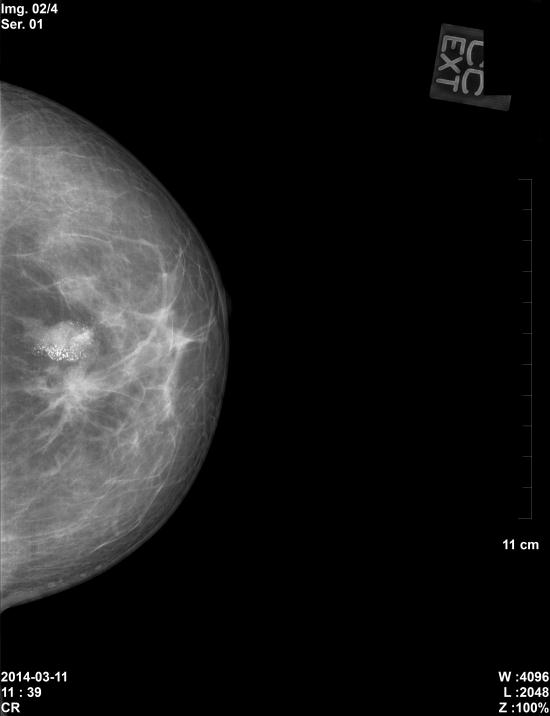

유방촬영(유방x-ray) 상 좌측유방의 미세석회회와 종괴소견있었고,

본원 초음파상 좌측유방 11:30분방향, 12시방향, 2시방향에

악성으로 의심되는 종괴소견있어 조직검사결과

상피내암 및 침윤성 유관암으로 진단되었습니다.